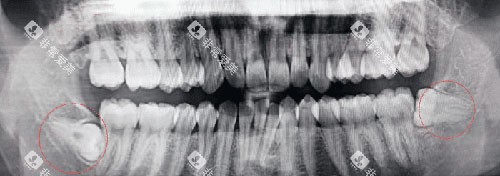

一走进医院,就能看到各种新型的口腔医疗设备,像CBCT机、全景机、激光设备啥的,这些可都是给诊疗效率和精细度加分的“神器”。

医院擅长的口腔治疗项目可多了,牙齿矫正、牙齿美白、根管治疗、牙齿种植等等,都能轻松应对。